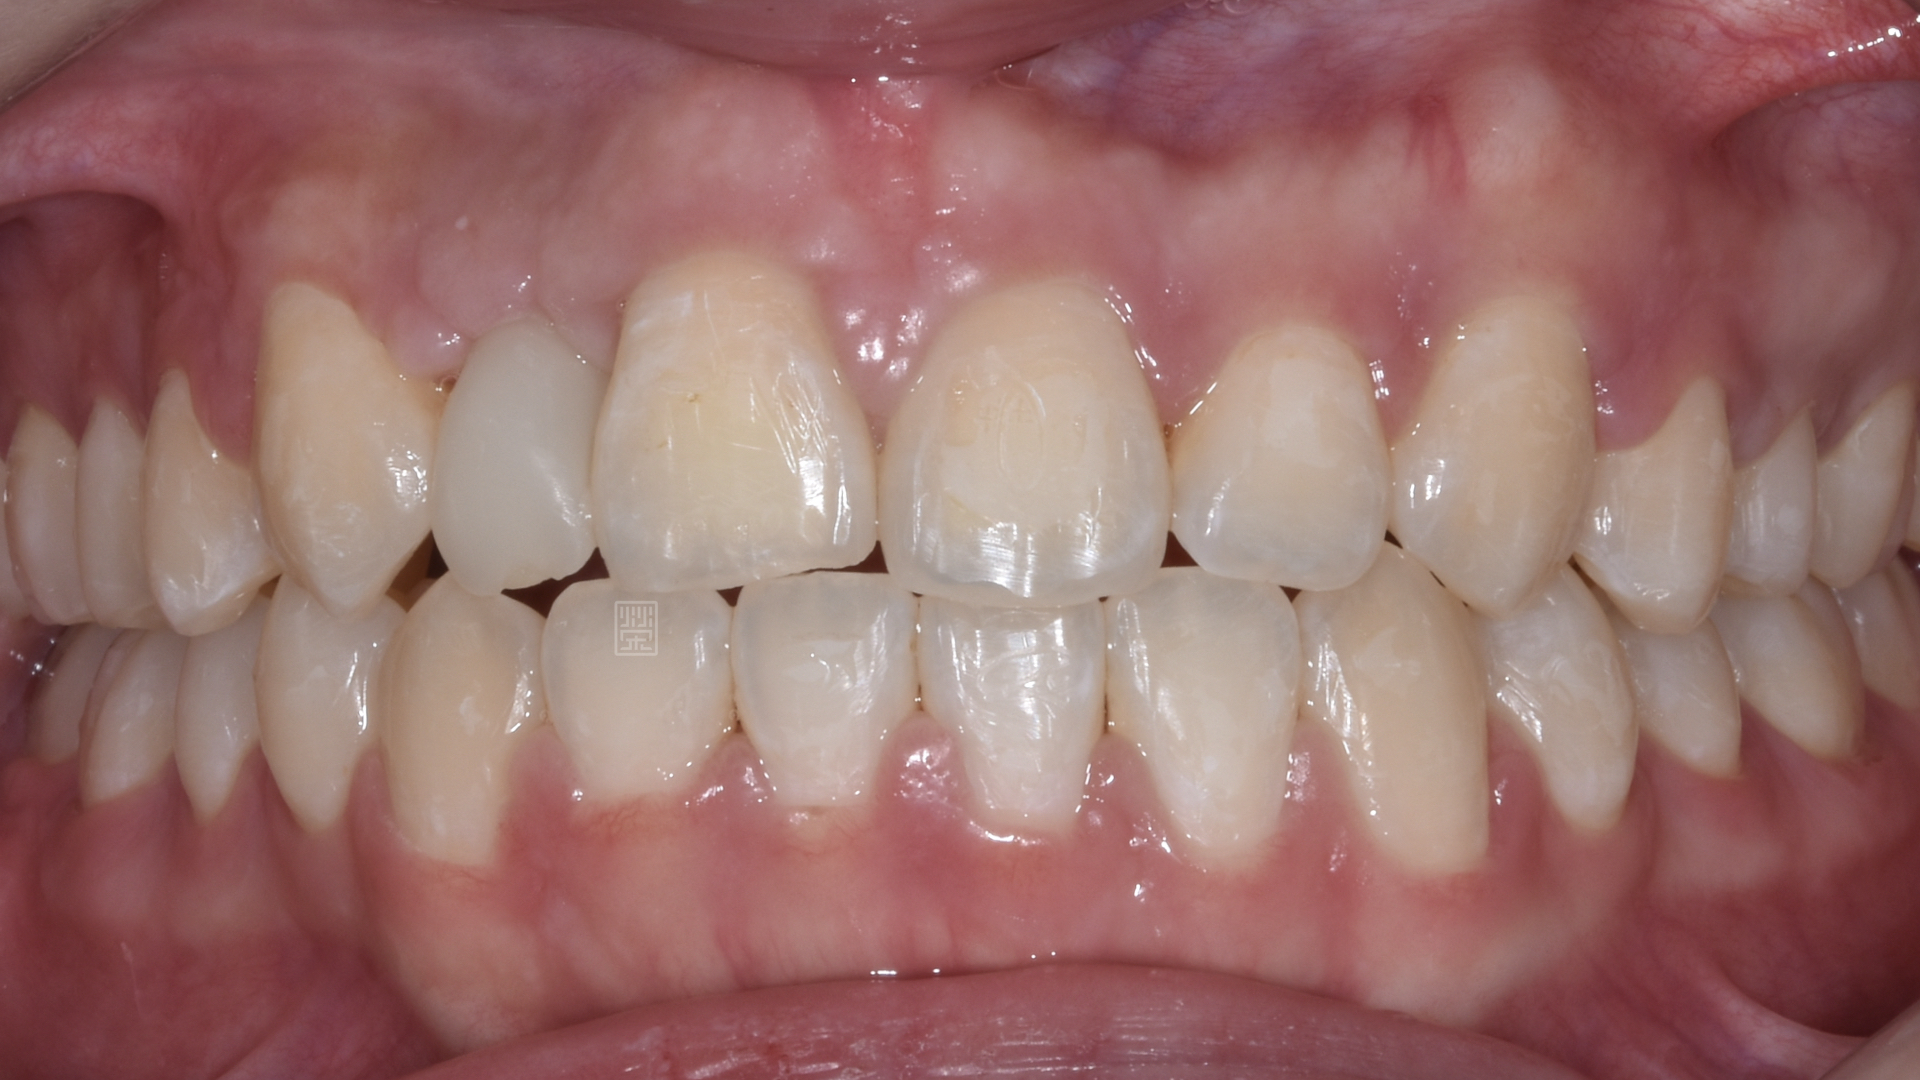

治療前牙齒因車禍有縫且缺牙

長期缺牙側門牙空間不足